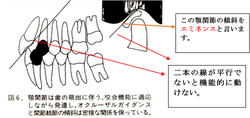

顎関節の機能と上顎前歯の傾斜の関係

下に示す図は、顎関節と上顎前歯の傾斜関係が2本の平行線により表されています。

上記の様に出っ歯(上顎前突)と顎関節は表裏一体の関係にあります。

この為、子供の時には何の障害も感じないのですが大人になってから顎関節症や無呼吸などの症状を引き起こす確率が高くなります。

出っ歯(上顎前突)は子供の時期に治療しておくことが良い症例と言えます。